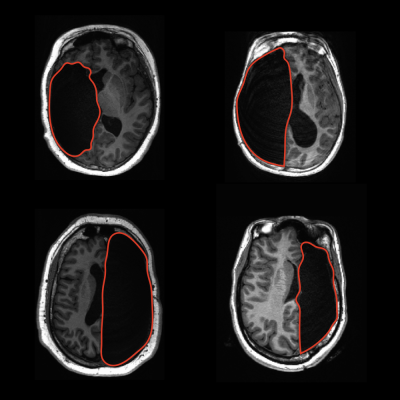

Examples of a single hemisphere in four children after surgery to manage drug-resistant epilepsy. Top row: Removal of the left hemisphere. Bottom row: Removal of the right hemisphere. Image credit: Sophia Robert